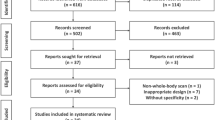

Model architecture, training and testing

The training and validation datasets are composed of 1203 and 164 images respectively, coming from Centre A (Aachen) and B (Aalborg). The external test cohort is composed of 998 images collected at centre C (Namur). A full overview of the patients cohort division between the different datasets is reported in Table 1.

The model was trained on 329 images containing metastasis from Centre B (94) and A (235). At each epoch, the 874 images without any metastasis were shuffled and 329 images were randomly selected to train the model with balanced labels. VGG16 architecture with ImageNet pretrained weights [21] was trained with categorical cross entropy loss for 6 epochs with 200 steps per epoch. The model was trained with 3 channel input. The pre-processed input was duplicated in all the channels, concatenating the inputs along the whole channels dimension to match the size of the pretrained ImageNet. During the training, the images were augmented [22] by flipping along the vertical axis so that the views at AP and PA were randomly represented in the left or right in the images.

The last Max Pooling layer in the VGG16 model was followed by a Global Average pooling layer, followed by a fully connected layer with 512 units and ReLu activation, which is followed by a classification layer containing 2 units with Softmax activation [23] as shown in Fig. 2. The network weights are updated by using the Adam optimizer at learning rate of 1e− 4 [24]. The trained model’s performance was evaluated on an external test dataset (n = 998).

The architecture used in the study. Pre-processed BS scans resized to 512 * 512 dimensions were provided as input to the network. The network outputs a probability score for presence and absence of metastasis on BS images. X = block repetitions, Conv = Convolution kernel, ReLU = rectified linear unit, 3 × 3 = the size of the 2D CNN kernels

The following software packages were used: Python v3.6, Keras v2.0.6 for modelling, training and validation and Sklearn v1.1.1 for metrics calculation and results visualization. The model was trained and validated on a 11GB NVidia GeForce GPU.

Quantitative metrics

The quantitative model performance in this study was assessed using ROC AUC, sensitivity and specificity of the classifier and confusion matrix (true positive rate (TPR), true negative rate (TNR), false negative rate (FNR) and false positive rate (FPR)). The model was evaluated according to the Checklist for AI in Medical Imaging (CLAIM) [25] and Standards for Reporting Diagnostic accuracy studies (STARD) [26].